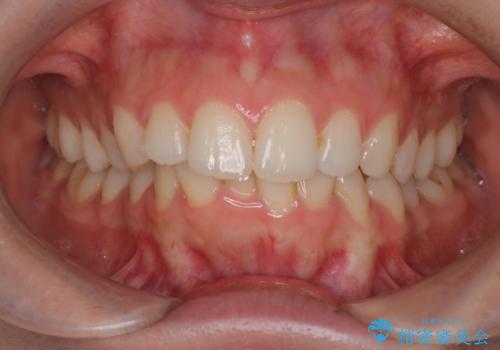

【インビザライン】前歯のガタガタをなおしたい。

- 前歯の凸凹を主訴に来院されました。

インビザラインにて奥歯の遠心移動を行いながら、前歯のガタガタを改善することができました。